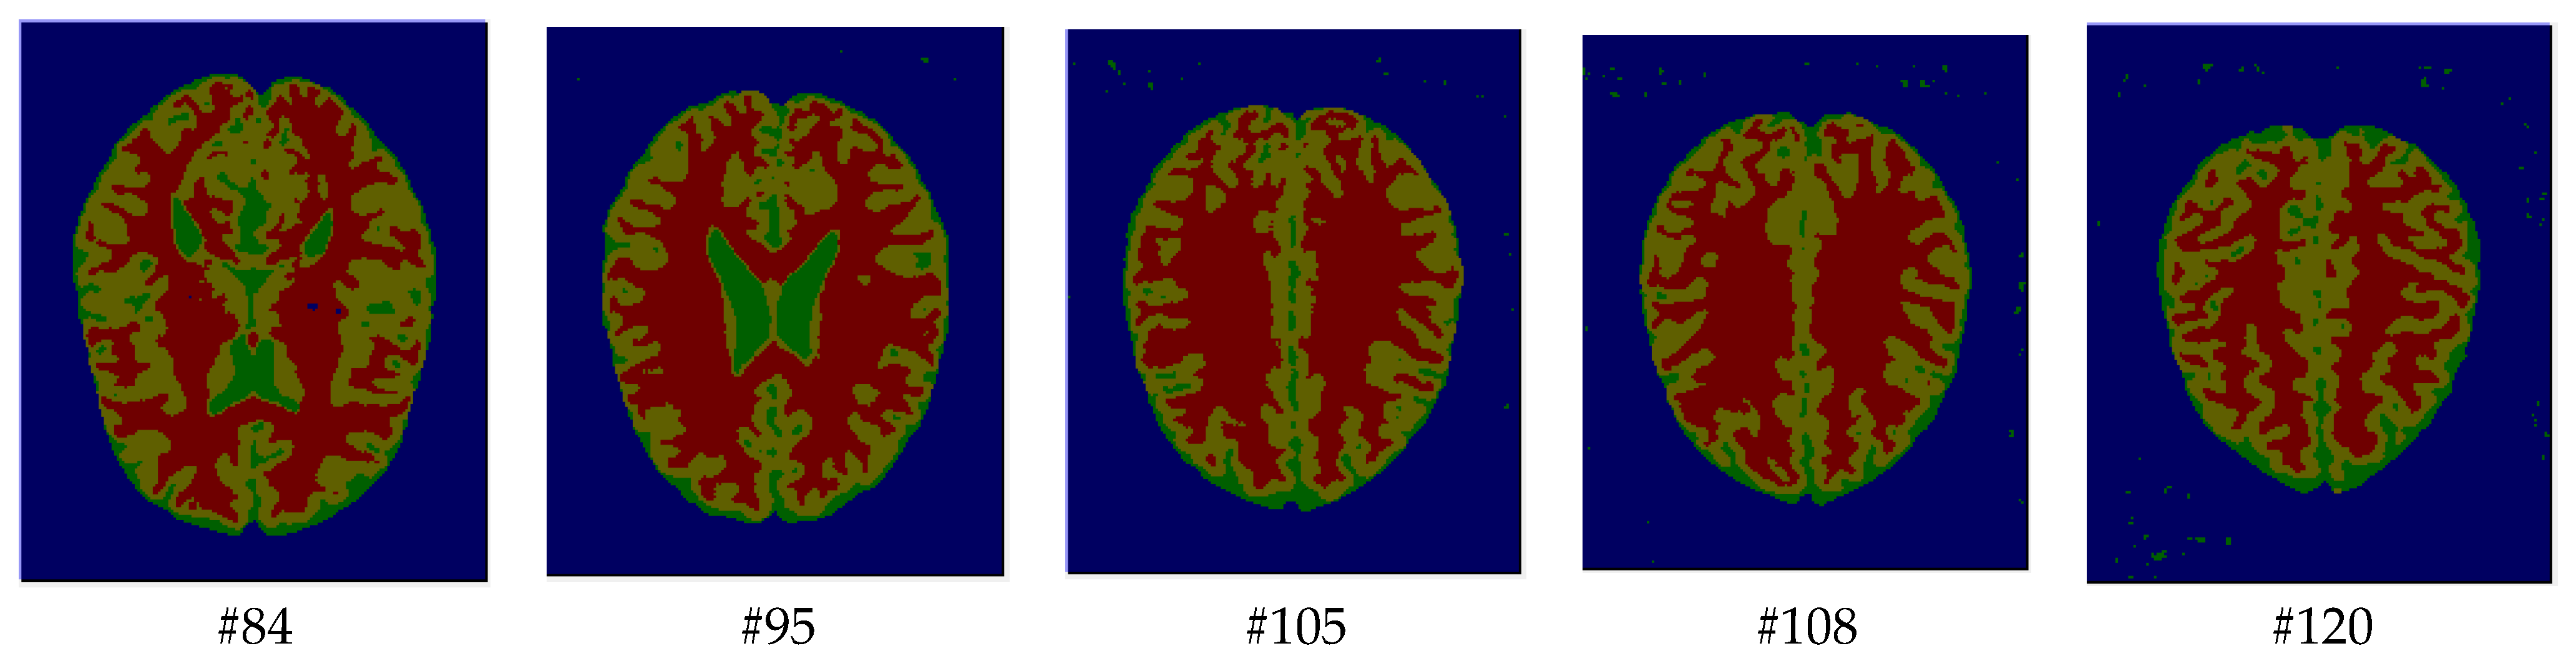

As mentioned before, the images of the first five datasets in Table 3 were used to evaluate the performance of the HMRF-WOA. Figure 1, Figure 2, Figure 3, Figure 4 and Figure 5 show some slices of a T1-weighted image (slices: 84, 95, 105, 108, 120). These brain images correspond to the slices under different types of conditions, such as database type, dimension image, noise level, intensity non-uniformity level, and slice thickness (mm). In Table 1, rows 1 to 5 summarize the parameters of Figure 1, Figure 2, Figure 3, Figure 4 and Figure 5, respectively. Figure 6 represents the ground truth segmentation of slices 84, 95, 105, 108, and 120. In this figure, each column contains the three tissues, GM, WM, and CSF, of each slice. Figure 7, Figure 8, Figure 9, Figure 10 and Figure 11 show the segmentation results, where the four tissues (BG, GM, WM, and CSF) are shown with different colors. The yellow, red, and green colors represent the segmented regions of GM, WM, and CSF, respectively. As we can also see from these figures, the resulting segmented images in Figure 7, Figure 8, Figure 9, Figure 10 and Figure 11 are almost close to the initial images in Figure 1, Figure 2, Figure 3, Figure 4 and Figure 5.

Figure 7. Segmentation results of the slices illustrated in Figure 1.